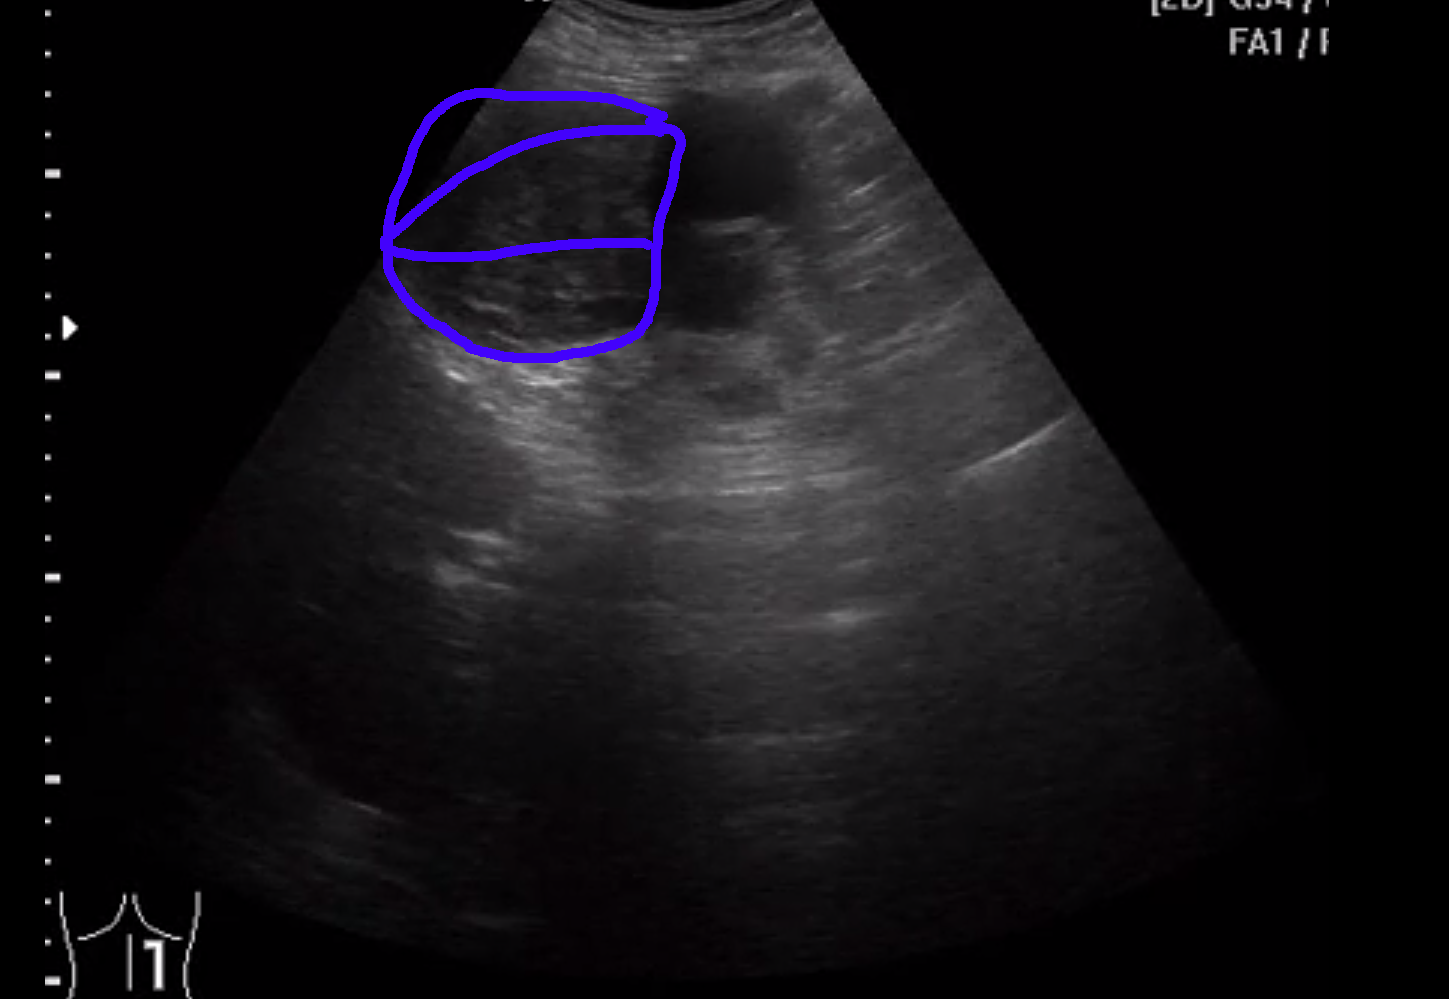

Вот здесь видно

Слева <-- видна опухоль (синий цвет в снэпшоте внизу), а справа -> почка со угадываемыми очертаниями.

из последнего клипа

Красная стрелка - сосуд или сосуды, тумор - синий цвет.